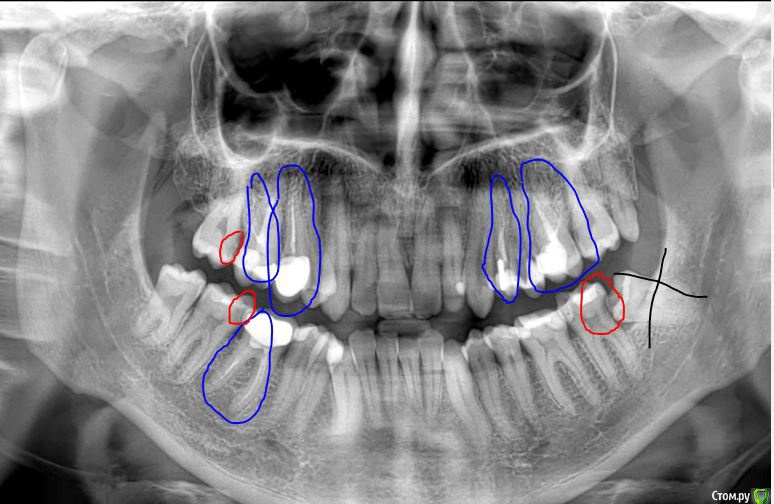

St. Опубликовано 20 июля, 2020 Поделиться Опубликовано 20 июля, 2020 Нет, просто не всегда и не у всех есть время и возможность быстро ответить.. Как минимум то что отметила на снимке, при очном осмотре возможно еще какие-то вопросы.По важности :1. удалить зуб мудрости слева внизу2. полечить кариес в живых зубах (отмечено красным но может еще где-то есть), в первую очередь низ справа и слева3. перелечить зуб под коронкой внизу справа4. перелечить и запротезировать остальные зубы без нерва с некорректно заполненными каналами (отмечено синим) Ссылка на комментарий

Alexm Опубликовано 1 августа, 2020 Автор Поделиться Опубликовано 1 августа, 2020 Нет, просто не всегда и не у всех есть время и возможность быстро ответить.. Как минимум то что отметила на снимке, при очном осмотре возможно еще какие-то вопросы.По важности :1. удалить зуб мудрости слева внизу2. полечить кариес в живых зубах (отмечено красным но может еще где-то есть), в первую очередь низ справа и слева3. перелечить зуб под коронкой внизу справа4. перелечить и запротезировать остальные зубы без нерва с некорректно заполненными каналами (отмечено синим)Спасибо большое за Ваш ответ! Ссылка на комментарий